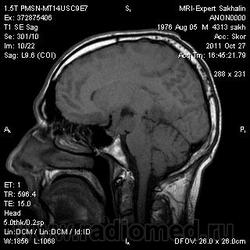

Помогите разобраться!Образование головного мозга.

Мужчина без направления.Жалобы на потерю памяти,шум в ушах в течение последнего года.

Заподозрила образование  из сосудистого сплетения заднего рога бокового желудочка  .Смещение срединных структур.Здесь отек смешанного типа?

Вряд ли это из желудочка, височный рог (кажется) виден на одном из сканов, он не расширен. Скорее всего глиальная опухоль. А то, что выглядит как асширенные сосуды - скорее всего кистозные полости.

Обычно опухоли желудочков вызывают регионарную гидроцефалию.

Не характерный тип накопления при эпиндимоме (если подозреваете желудочек),  и тем более для сосудистой неоплазии, к тому же слишком большой мягкотканный компонент.

Отсутсвие накопления  позволяет предположить глиальную опухоль высокой степени дифференцировки.

Согласен с Евгением. Больше похожа на анапластическу глиому - астроцитому или олигодендроглиому. У глиобластомы, как правило, преобладает кистозный компонент.

Передумал, под аргументрованными высказываниями мудрых товарищей - глиома или астроцитома...